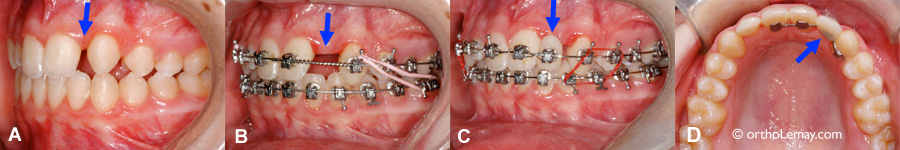

Apparition de caries entre des dents antérieures pendant l’orthodontie-1

(A et B) La rotation de deux centrales camoufle une carie entre ces dents. (C) La carie est visible vue de l’intérieur de la bouche. (D) Après les corrections orthodontiques et la réparation de la carie.